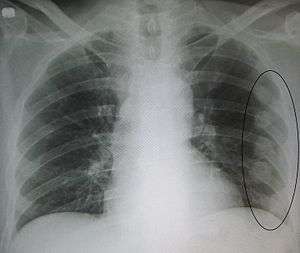

- Pneumothorax